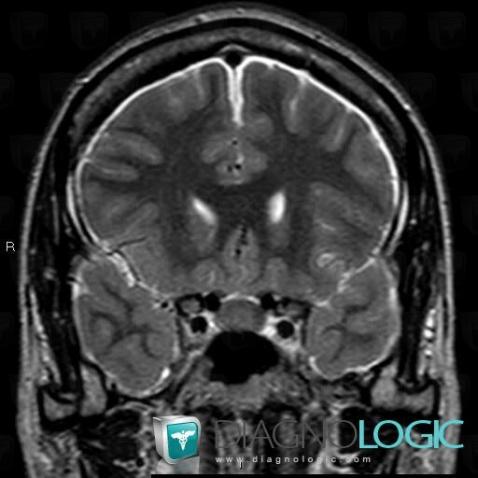

Voici les informations spécifiques à l'image clé ci dessus:

- Diagnostic Hypotension intracrânienne , Localisation(s) Espaces peri cérébraux infratentoriels, comportant les gammes Réhaussement méningé diffus